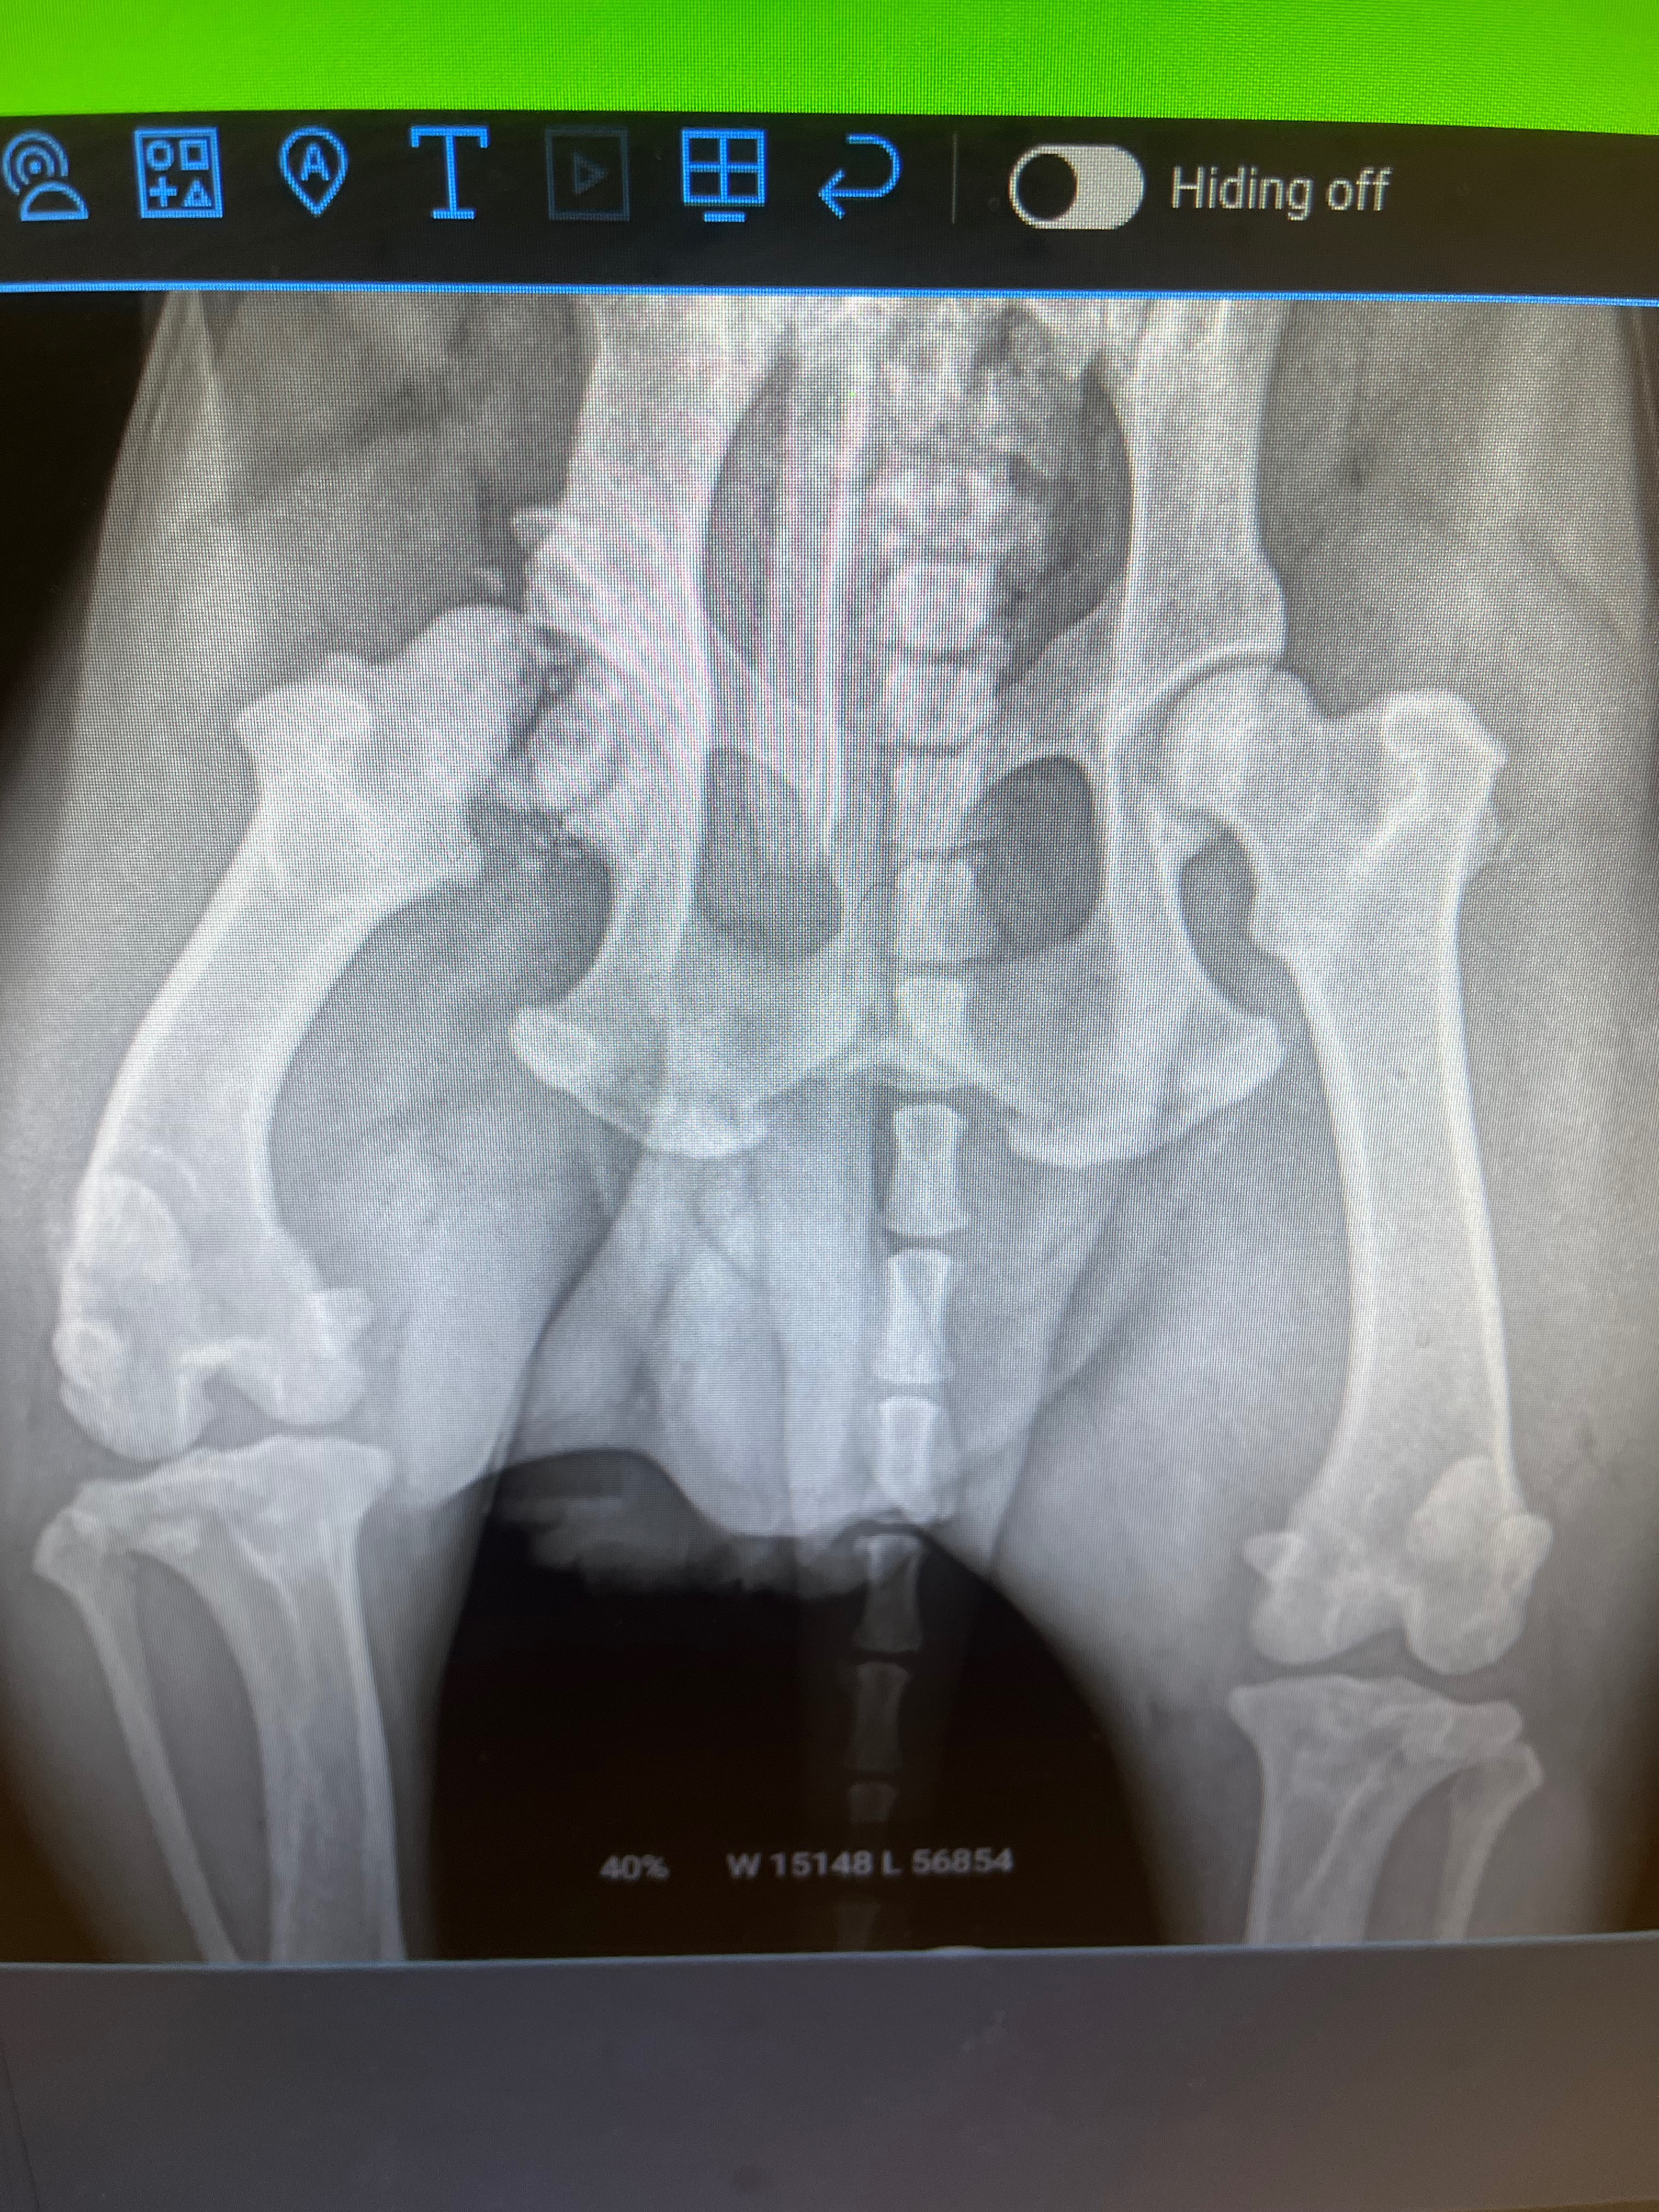

This cute little guy was found by a good samaratin, dumped in a field left with a bowl and a bag of dog food! Instantly trusting of humans he hopped in their car to safety. Now Blackjack is in our care awaiting his forever home but he’s got a hurdle to cross: Upon intake we noticed he had a limp, and thru X-rays it was discovered that he had suffered an old injury breaking the top of his femur bone! An FHO surgery will go in and clean up the small bits of broken bone that is causing his discomfort and he’ll be ready to live out an active, happy life. Help us get this boy on the road to his bright new future!